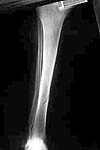

We have done the 2nd Fixion inflatable nail last Tuesday, for a 1st degree open distal tibial fracture. It was a 15 minute procedure and the patient walked next day out of the ward. The first patient had a eventful rehabilitation and was walking without crutches after one month (he was a polio patient on the operated limb). I am sending some pictures. Please note the hourglass shape of the inflated nail. I will keep the list informed of the follow up of those patients.